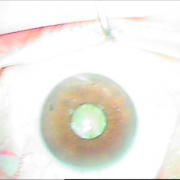

Οι σύγχρονες μικροχειρουργικές τεχνικές αποβλέπουν στον ελάχιστο τραυματισμό του οφθαλμού και στην τοποθέτηση του τεχνητού ενδοφακού στην φυσική του θέση που είναι ο οπίσθιος θάλαμος. Οι ασθενείς απολαμβάνουν τα πλεονεκτήματα των επεμβάσεων μικρής τομής χωρίς ράμματα, με άμεση αποκατάσταση της όρασης και χωρίς μετεγχειρητικό αστιγματισμό.